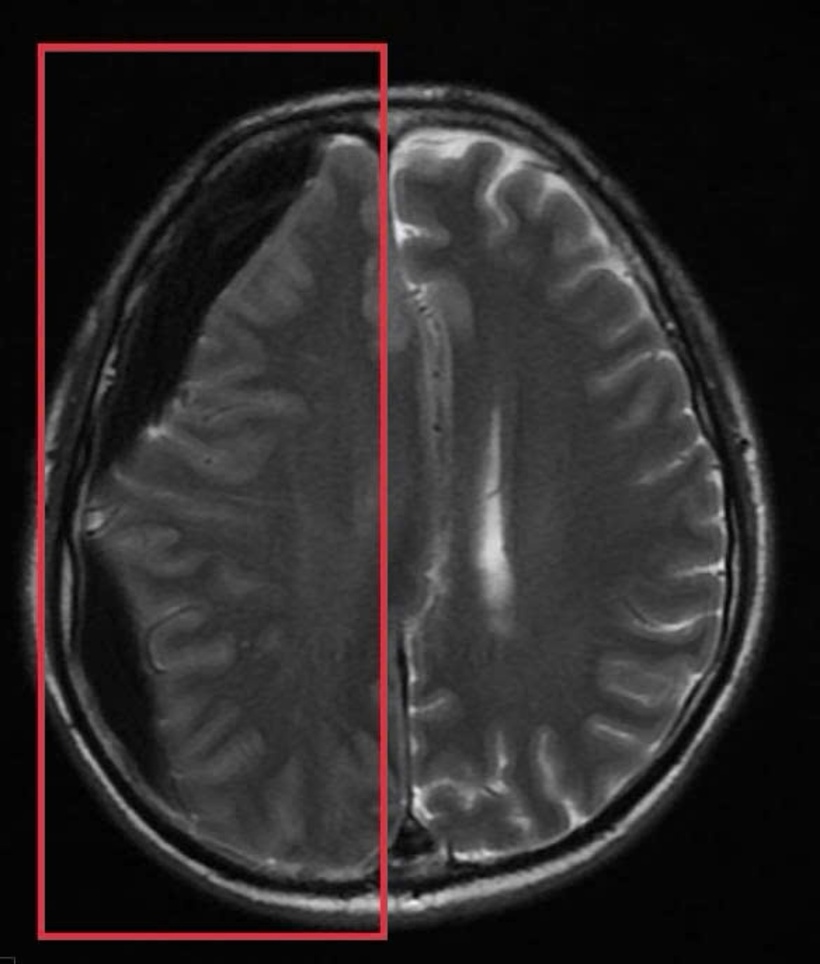

Trước băn khoăn của gia đình, BS Huyền đã tư vấn ưu tiên chụp MRI sọ não. Kết quả chụp MRI sọ não cấp đã xác định người bệnh có khối tụ máu não dưới màng cứng mạn tính kích thước lớn vùng thái dương, gây hiệu ứng khối và đè đẩy đường giữa của não. Đây là tình trạng đặc biệt nguy hiểm, bởi khối tụ máu có thể tiến triển âm thầm trong nhiều tuần với triệu chứng kín đáo như chậm chạp, giảm trí nhớ, rối loạn ngôn ngữ nhưng có nguy cơ cao dẫn đến liệt vận động, tụt kẹt não, hôn mê và tử vong nếu không được xử trí kịp thời

Khối tụ máu não dưới màng cứng mạn tính kích thước lớn vùng thái dương, gây hiệu ứng khối và đè đẩy đường giữa của não